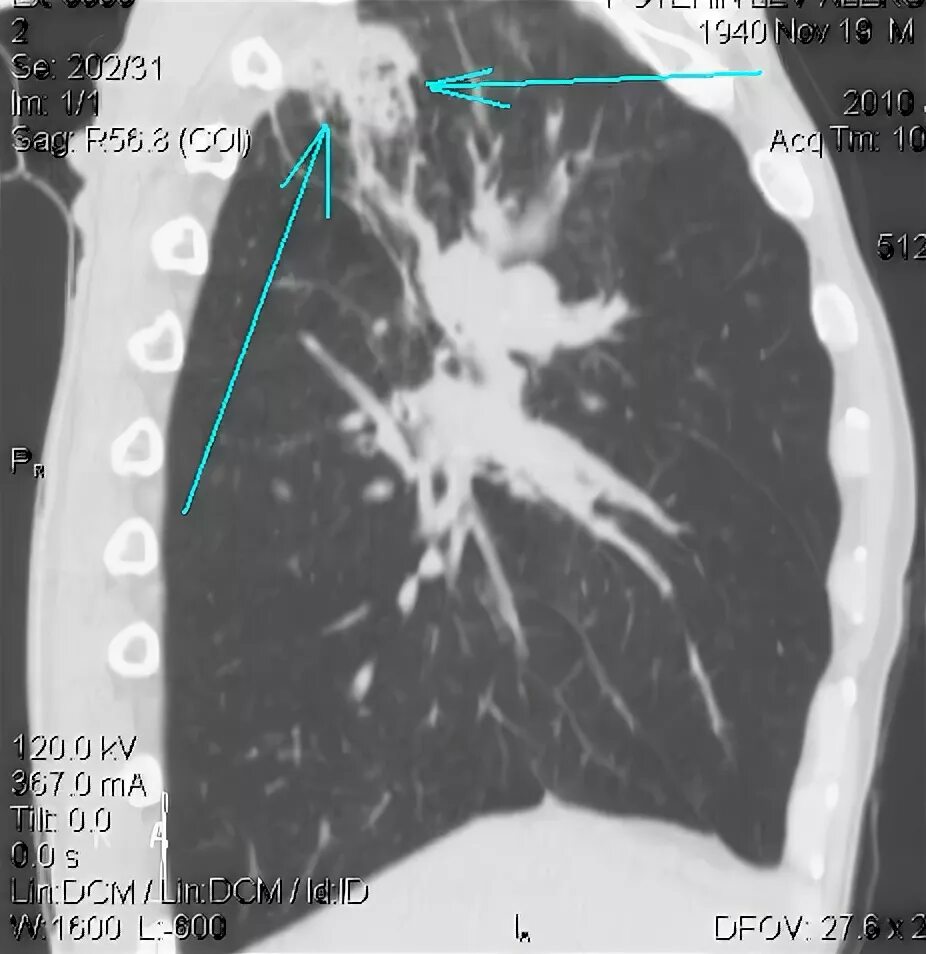

Метастазы в средостении легких